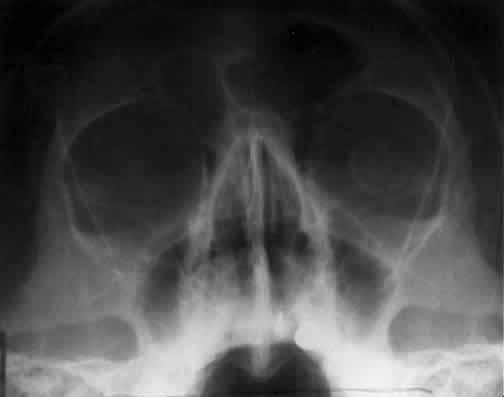

OPTIC FORAMEN (RHESE POSITION)

In 1911 Rhese14 described a projection (Fig. 6) for the evaluation of the ethmoid sinuses and the optic foramen. The patient is positioned with the orbit to be studied against the x-ray cassette. The zygoma, nose, and chin should touch the cassette. The x-ray beam is directed posterior-anteriorly at 40 degrees to the midsagittal plane.5,6 In this position the optic canal is in the inferolateral quadrant of the orbit and oriented perpendicular to the x-ray cassette.15 Variations of this standard position can be used to view other structures of interest. The Rhese projection allows assessment of the orbital apex, in particular, the optic foramen, optic strut, and the upper ethmoid sinus. A pneumatized anterior clinoid process may simulate the optic foramen. The landmark for finding the foramen is to find the planum sphenoidale; the optic foramen lies at its lateral end. The optic canal may be evaluated for expansion or compression by disease processes, such as optic nerve tumors (glioma and meningioma) and trauma. CT and magnetic resonance imaging show much better detail and therefore have replaced the use of plain films for evaluation of the optic canal.

Fig. 6. A and B. Schematic showing positioning for an oblique apical projection (Rhese position). (CR, central ray; CM, canthomeatal line) C. Radiograph of an oblique apical projection. (a, right optic canal; b, optic strut; c, superior orbital fissure; d, ethmoid sinus; e, planum sphenoidale; f, greater wing of sphenoid) (A and B; Rao VM, Gonzalez CF: Plain film radiography and polytomography of the orbit. In Gonzalez CF, Becker MH, Flanagan JC [eds]: Diagnostic Imaging in Ophthalmology, pp 1–7. New York, Springer Verlag, 1986)